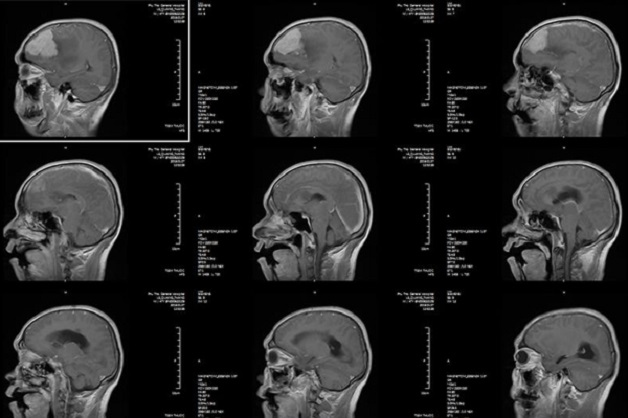

Chụp cắt lớp vi tính sọ não (chụp CT sọ não) là phương pháp dùng tia X để chụp hình ảnh đầu và mặt. Kỹ thuật chụp này sẽ cung cấp các hình ảnh về mắt, xương mặt, khoang chứa khí (xoang) trong xương gần mũi và tai trong. Do đó, chụp CT sọ não thường được dùng để giúp bác sĩ đánh giá các bệnh lý liên quan đến các bộ phận ở phần đầu mặt trên cơ thể.

Chụp CT sọ não là phương pháp dùng tia X để chụp hình ảnh đầu và mặt